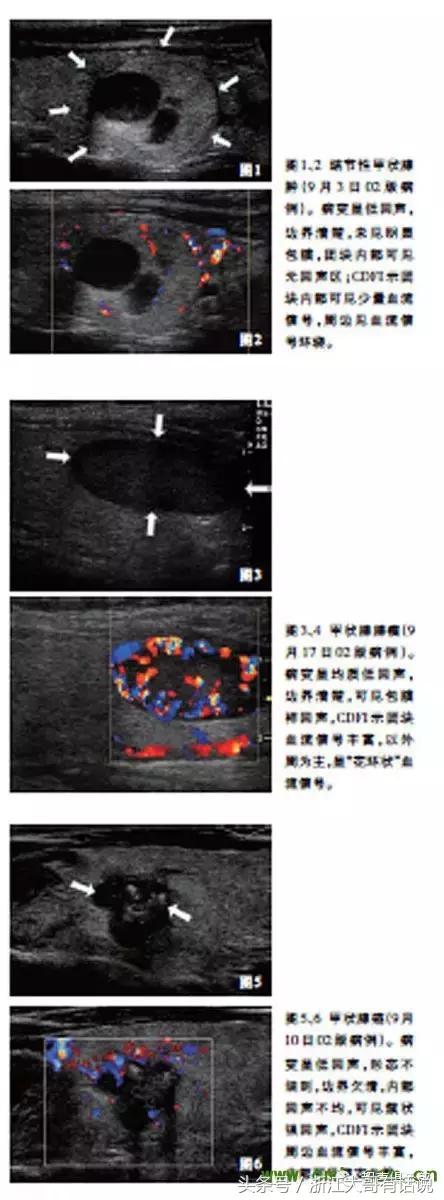

图1、2 结节性甲状腺肿(9月3日02版病例)。病变呈低回声,边界清楚,未见明显包膜,团块内部可见无回声区;CDFI示团块内部可见少量血流信号,周边见血流信号环绕。

图3、4 甲状腺腺瘤(9月17日02版病例)。病变呈均质低回声,边界清楚,可见包膜样回声,CDFI示团块血流信号丰富,以外周为主,呈“花环状”血流信号。

图5、6 甲状腺癌(9月10日02版病例)。病变呈低回声,形态不规则,边界欠清,内部回声不均,可见簇状强回声,CDFI示团块周边血流信号丰富,内部可见穿支血管。